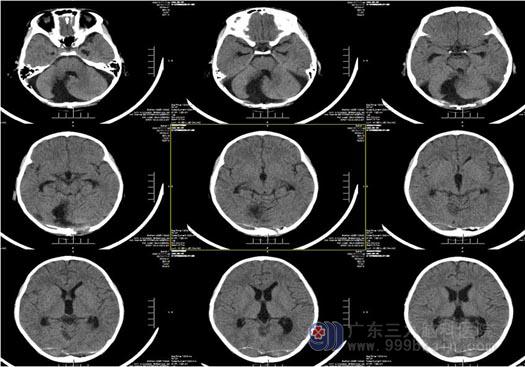

▲术后CT:脑积水已较术前明显缓解

▲术后病理结果:毛细胞星型细胞瘤(WHO I 级)

毛细胞性星形细胞瘤属于WHO 分类I级的神经上皮性肿瘤,也可以叫I级胶质瘤,是良性肿瘤,可以单纯通过手术治疗而治愈。最常发生于儿童和青年人,可见于大脑半球、下丘脑、前视路、脑干、小脑和脊髓。在幕上最常发生于前视路及下丘脑,一般呈实体性,在幕下最常发生于小脑半球,一般呈囊性伴囊壁或囊旁的瘤结节,这种肿瘤不是一般的胶质瘤,若手术切除干净了,一般是不再会复发。